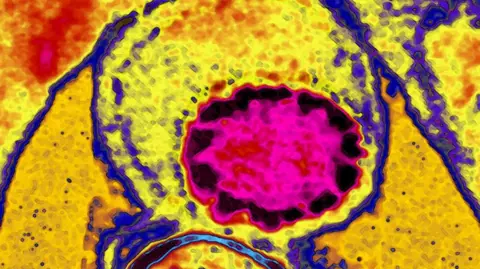

Vascular surgery involves complex procedures including angioplasty as shown in this CAT scan image showing an arterial stent